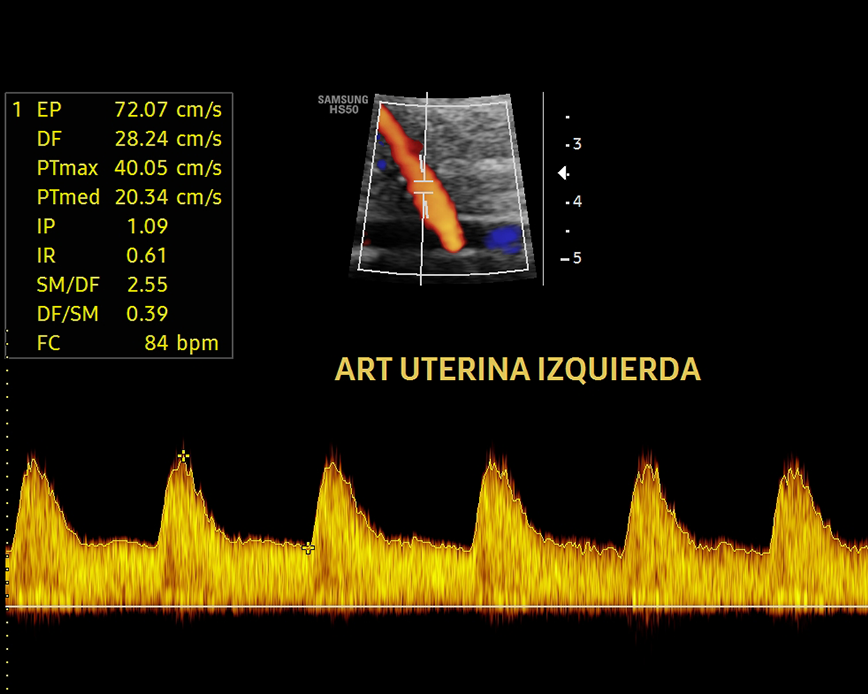

Esta ecografía sirve para evaluar la hemodinamia materno-fetal y detectar problemas de crecimiento como el RCIU (Restricción del Crecimiento Intrauterino) y el riesgo de preeclampsia (presión arterial alta durante el embarazo). Además, nos permite evaluar el cordón umbilical y detectar circulares de cordón simple, doble o triple.